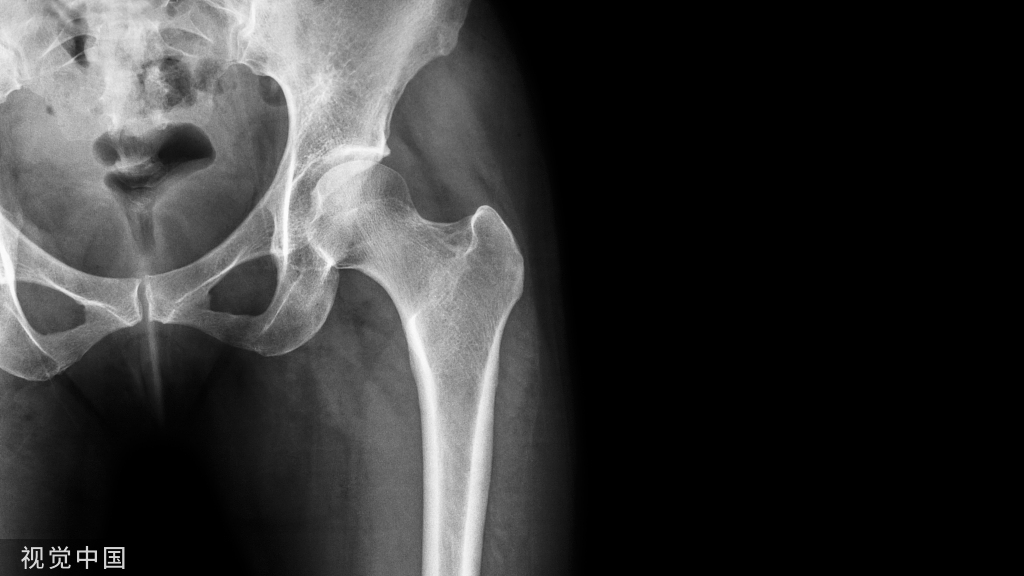

它与腰骶部疼痛存在密切的相关性是不可忽视的, 并干扰诊断与之症状相近的其它疾病, 如椎间盘突出、致密性骨炎、强直性脊柱炎等等, 当然这其中有些疾病可以并存, X 线、CT 检查在腰骶部移行椎的诊断中有重要意义, 不仅能对本病做出诊断, 并且有助于鉴别诊断。